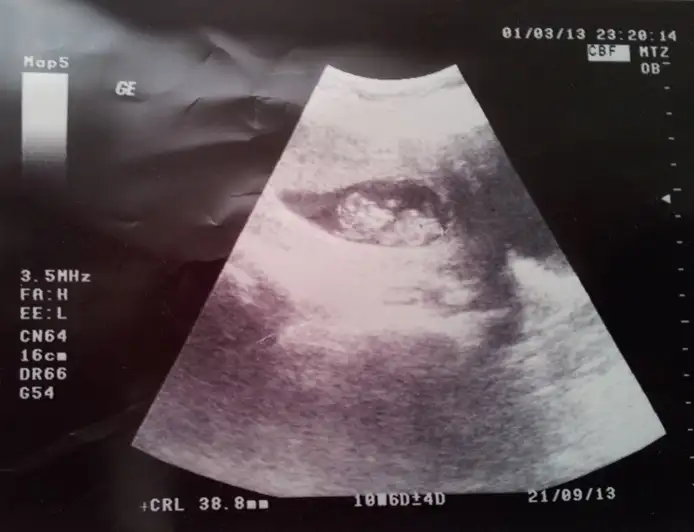

11+4 deki ultrasonumuz, ORKDM yorumlarmısın lütfen

11 haftlar genelde yaniltiyor ama

yari yariya seninki

kiz nubu var lakin buyuk ve yuksekte

bu durumda kizdan erkege donecek nublar gibi

baska varsa gorelim